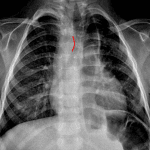

Age: 3

Sex: Female

Indication: Choking, history of esophageal atresia repair

- Patulous, gas-filled esophagus with gradual tapering distally near the gastroesophageal junction. Lobular soft tissue density in the mid esophagus

- No focal airspace opacification, pleural effusion, or pneumothorax

- Borderline enlargement of the cardiothymic silhouette

- Right aortic arch

- Impacted food bolus

- Right aortic arch

Patulous, gas-filled esophagus with gradual tapering distally near the gastroesophageal junction. Lobular soft tissue density in the mid esophagus is concerning for impacted food bolus.

No focal airspace opacification, pleural effusion, or pneumothorax.

Borderline enlargement of the cardiothymic silhouette.

Right aortic arch. Consider cardiology referral if this finding has not been previously evaluated.